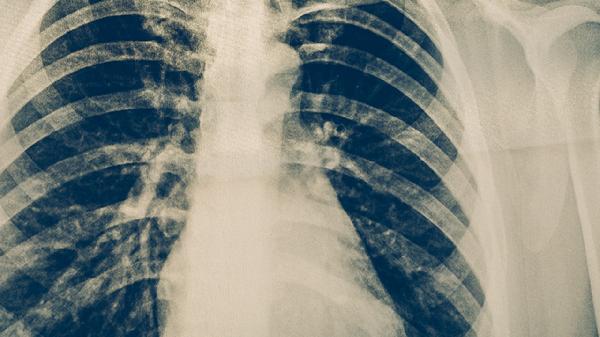

肺结核患者可通过呼吸道隔离、环境消毒、个人防护、接触者筛查、规范治疗等方式实现有效隔离。肺结核是由结核分枝杆菌引起的慢性传染病,主要通过飞沫传播。

确诊患者需单间隔离或集中收治于负压病房,佩戴口罩阻断飞沫传播。住院期间限制探视,患者咳嗽时用纸巾遮掩口鼻,痰液需经含氯消毒剂浸泡处理。隔离期持续至痰涂片转阴且临床症状改善,通常需要2-4周强化治疗期。